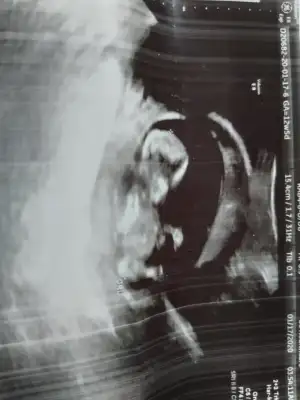

dr soylemeden siz gorun genital nub teorisi ( bebegin cinsiyeti)

Sevgili İkra,

Yorumlarsan çok sevinirim. ☺️❤️